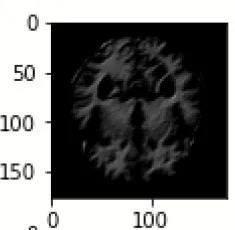

The database used in this study consists of a total of 6,200 AD images that are retrieved from the Kaggle database. It comprises grayscale images of 896 MD, 64 Mod D, 3,200 ND, and 1,966 VMD images, with a dimension of (208 × 176 × 3) pixels. The dataset for evaluation is divided in such a way that 80% of the image samples are utilized for training the model and the remaining 20% are utilized for testing the model (Filipovych et al., 2011). Figure 2 shows the database of MRI images. Table 2 shows the publicly available AD dataset.

FIGURE 2

www.frontiersin.org

Figure 2. Alzheimer's disease: (A) M.D, (B) Mod.D, (C) N.D, and (D) V.M.D.